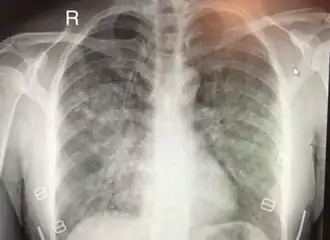

Œdème pulmonaire de haute altitude

L'œdème pulmonaire de haute altitude (OPHA) est une forme mortelle d'œdème pulmonaire (accumulation de liquide dans les poumons) non cardiogénique qui se produit chez les personnes en bonne santé à des altitudes généralement supérieures à 2 500 mètres[1]. Cependant, des cas ont également été signalés entre 1 500 et 2 500 mètres chez des sujets plus vulnérables.